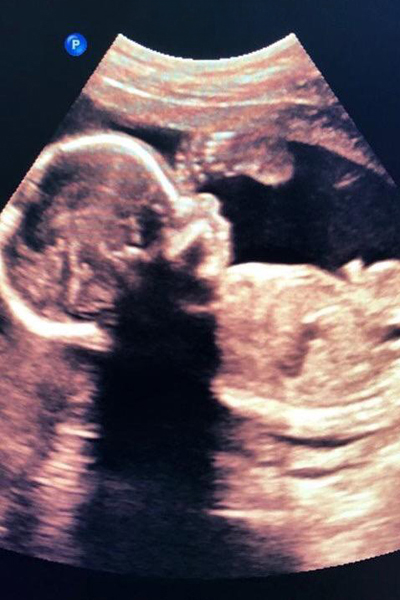

O exame de ultrassonografia é muito conhecido entre as gestantes, sendo fundamental para o acompanhamento do pré-natal, pois é seguro tanto para o bebê quanto para a mamãe.

Obstétrico

Em cada fase da gestação, desde o início até o nascimento do bebê, é importante acompanhar o crescimento e desenvolvimento geral. Realizamos todos os exames obstétricos indicados no pré-natal, entre eles o morfológico. Entre em contato e saiba mais.